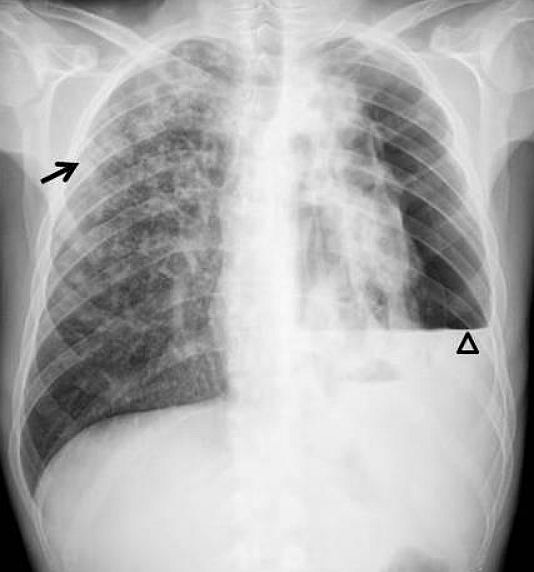

A 28-year-old male Spanish patient presented with weight loss and anorexia for one year, in association with dyspnoea, fever, cough, expectoration and left pleuritic pain during the past week. On physical examination during chest auscultation hypophonesis was noted on the left side.

What’s the diagnosis ?